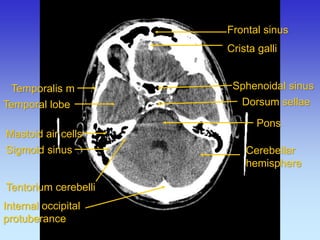

Frontal sinus

Pons

Mastoid air cells

Crista galli

Temporalis m

Temporal lobe

Cerebellar hemisphere

Sigmoid sinus

Internal occipital protuberance

Sphenoidal sinus

Dorsum sellae

Tentorium cerebelli